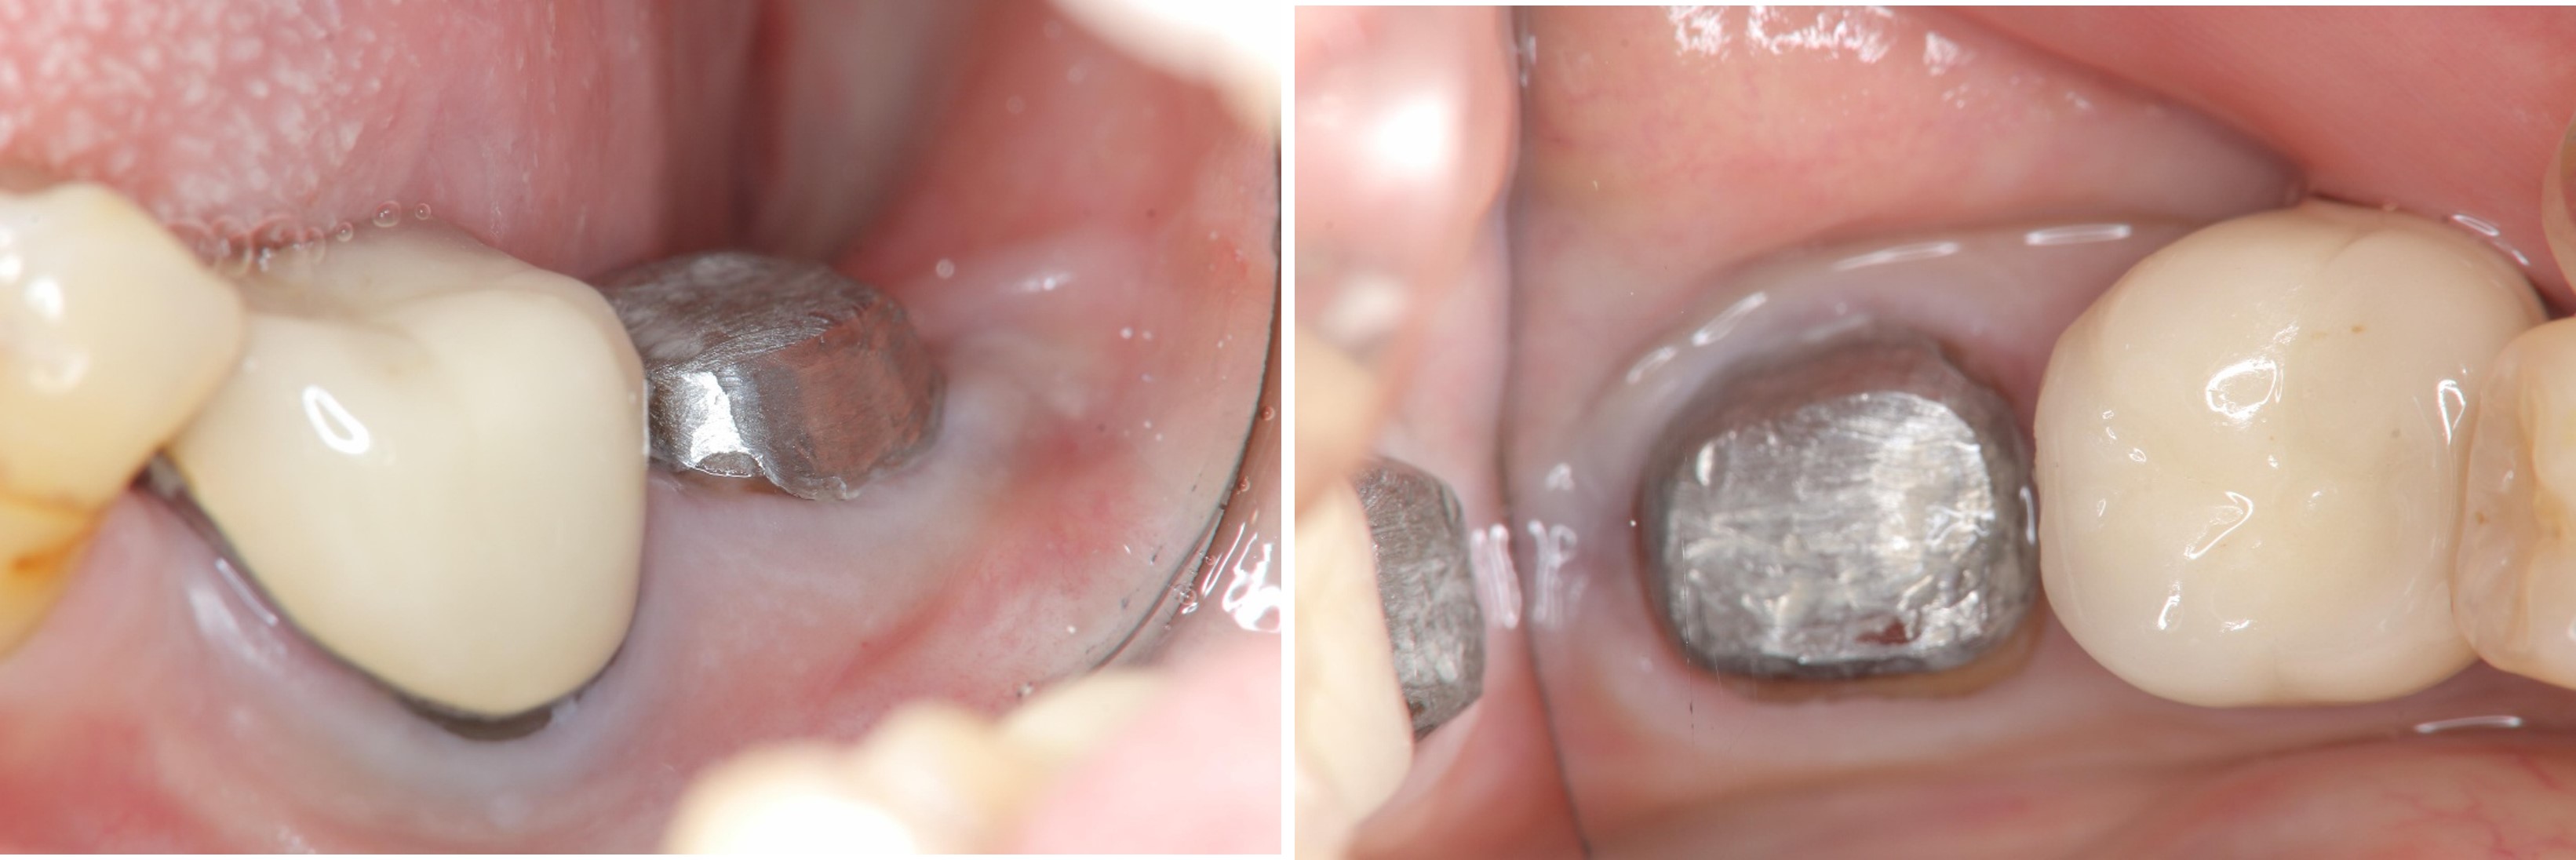

牙齒印模前追蹤